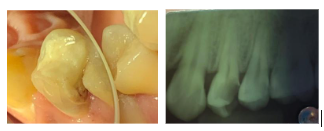

O exame clínico e radiográfico revelou uma lesão compatível com necrose pulpar no elemento 24, indicando a necessidade de tratamento endodôntico (Figura 1).

Figura 1. Aspecto clínico inicial do elemento 24 apresentando alteração de coloração e lesão de cárie profunda (A); radiografia periapical inicial evidenciando imagem radiolúcida periapical compatível com necrose pulpar (B).

Fonte: Imagem acervo do autor.